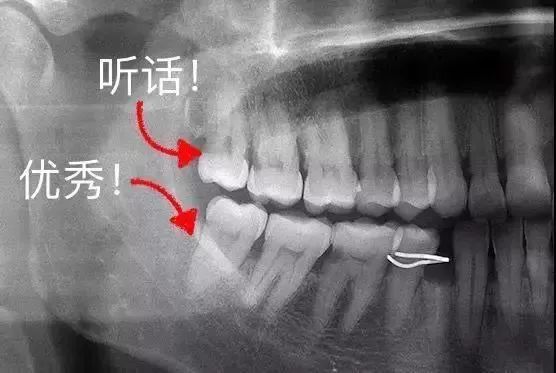

什么叫做“叛逆少年型”?看看下面的图片感受下——

看到没?

这些都是走了歪路的“叛逆少年”

那么,它们四周都危机四伏——

❶ 细菌的温床

不仅容易藏污纳垢、还有很多清洁死角!而久之,龋齿、冠周炎等口腔疾病就会找上门。

❷ 邻牙的瘟神

最惨的是智齿的“邻居”,轻则牙齿表面生成菌斑,重则整个牙为智齿“陪葬”。智齿甚至能把整副牙都挤歪。